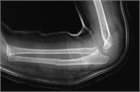

1. 尺骨骨折があった場合、橈骨頭脱臼を見流さないことがポイントである。

1. 見逃された陳旧例では前腕の回旋運動と肘の屈伸運動が障害される可能性があるため、できるだけ早く専門医に紹介する。